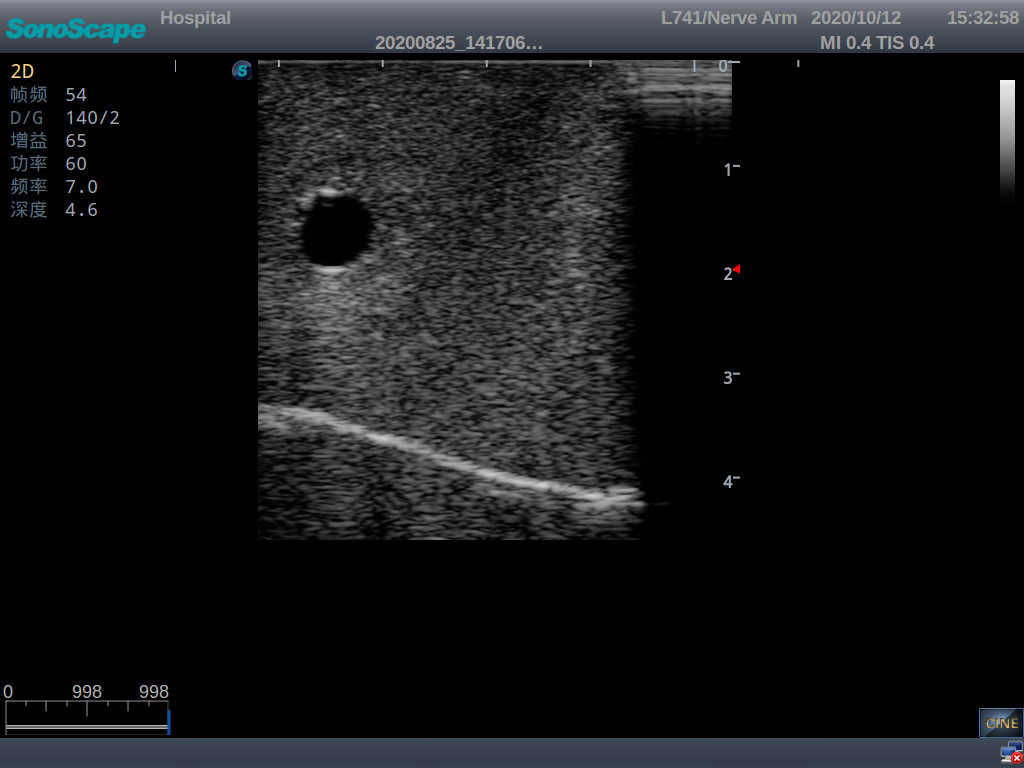

Central Venous Catheterization Ultrasound Training Model

Model TYE1510.2

It is a model from the earlobe plane to the umbilical plane with its head turned to one side. It's put in a standard central venipucture and catheterization position, including landmarks such as right arm, clavicle, ribs, sternocleidomastoid muscle, sternoclavicular joint, etc. It can be used for ultrasound-guided subclavian vein and internal jugular vein puncture and catheterization. The model's arm can be used for ultrasound-guided PICC catheter placement.

· Anatomy:

Right internal jugular vein, right common carotid artery, superior vena cava, right brachiocephalic vein, right brachiocephalic trunk, right subclavian vein, right subclavian artery, etc.

· Key Features:

1)  The module for central venous catheterization is transparent, allowing users to clearly see the course and adjacent relationship of blood vessels

2)  The puncture module supports using a clinical real ultrasound machine to observe clear images such as right internal jugular vein, right common carotid artery, superior vena cava, right brachiocephalic vein, right brachiocephalic trunk, right subclavian vein, right subclavian artery, etc.

3)  The puncture pad at the arm is made of high-molecular ultrasound material, close to real skin. It can support the use of real ultrasound machines, and the images of tissue structures (skin, subcutaneous tissue, blood vessels) under ultrasound are clear and real